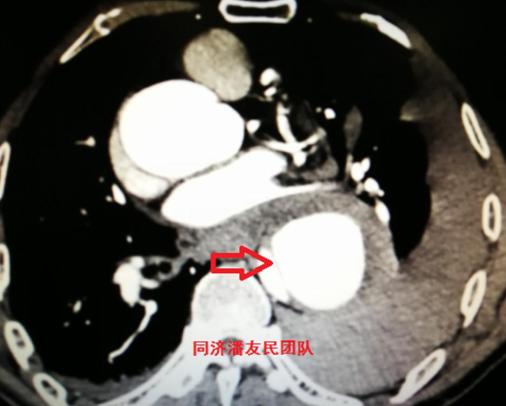

于是,胸腹主动脉CTA被安排(图3~5),结果显示夹层病变从升主动脉远端开始,累及到主动脉弓部,其中左颈总动脉及左锁骨下动脉均累及。